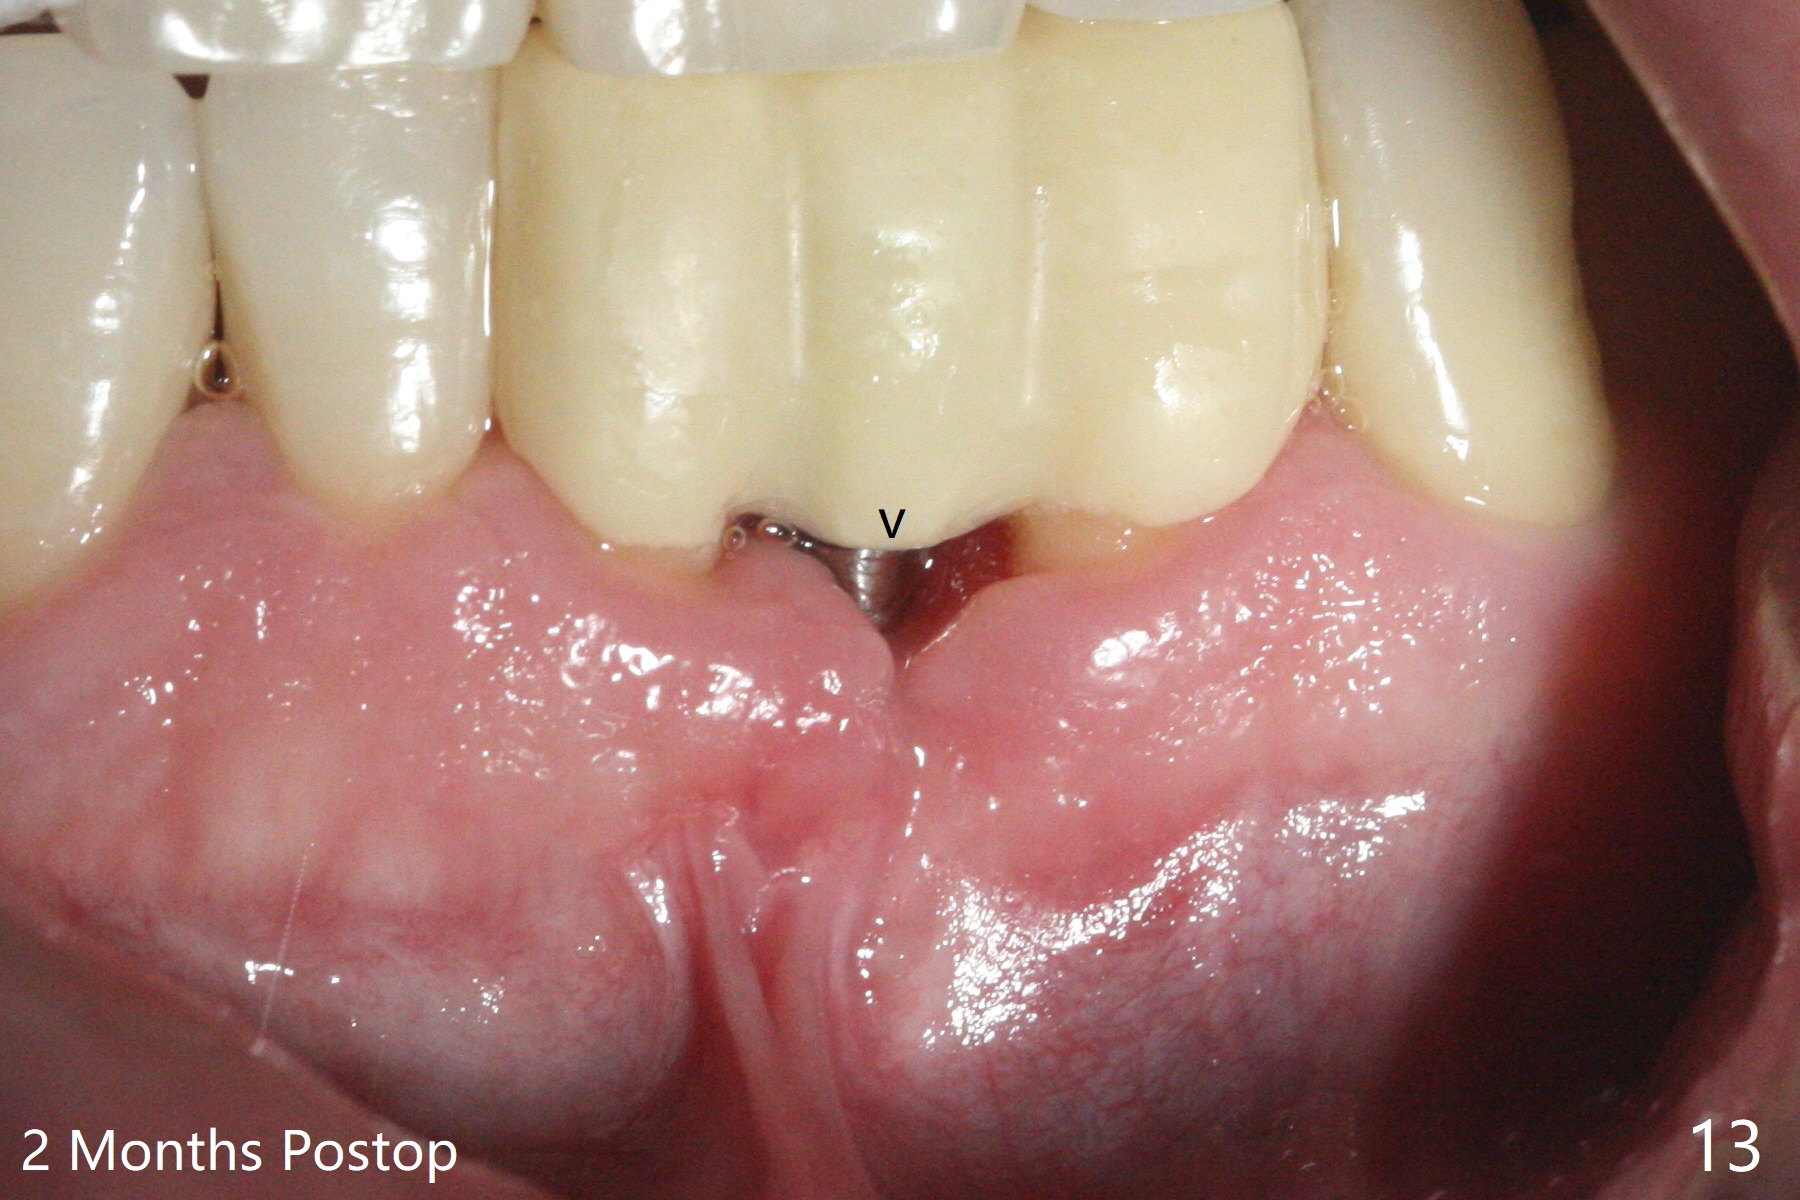

经过深洗以及改善口腔卫生,术前下前牙区牙龈基本没有红肿,但是缺牙处牙龈凹陷(图一,二:箭头),这个现象代表什么?如何影响手术进路?其实后者部分是因为牙龈与下面骨质(骨嵴)粘连(图三:*)产生的,分离粘骨膜瓣时不小心撕裂颊侧牙龈(图三(骨膜分离器下面:#),造成后来缝合困难,需要多用一个胎盘膜)。如果术前仔细分析CT 3D图像(图四,五)可以发现严重颊侧骨壁凹陷(图三:^)以及骨嵴(图四:*),事先抽血制备PRF膜和粘性骨粉,植骨效果好些(图六)。术中发现缺损,再抽血会拖延手术。最后将就用血调袢骨粉,使用胶原膜和胎盘膜覆盖(图七,八)。颊侧裂口术后十天愈合了(图九,十)。术后一个月颊侧牙龈凹陷,牙桥边缘(图十一:箭头)粗糙,临时牙桥取出,调整边缘,有利于局部卫生(图十二)。术后两个月桥边缘光滑(图十三:箭头),局部卫生和牙龈凹陷有所改善。病人将一个半月后回来取模。Return to Protect Graft 前磨牙即种 101 Xin Wei, DDS, PhD, MS 1st edition 04/30/2021, last revision 07/03/2021